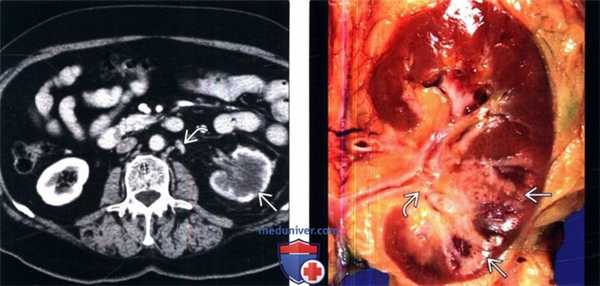

(Слева) КТ с контрастированием, аксиальная проекция: инфильтрация почечной паренхимы агрессивным переходноклеточным раком. Локализация опухоли -нижняя чашечка, которая при пиелографии выглядит как «выключенная». Контур почки сохранен. На смежных изображениях видны узловые метастазы.

(Справа) Макропрепарат удаленной почки (коронарная плоскость): у этого же пациента обнаружена опухоль вдоль поверхности собирательной системы нижнего полюса, прорастающая в паренхиму, с сохранением нормального контура почки.